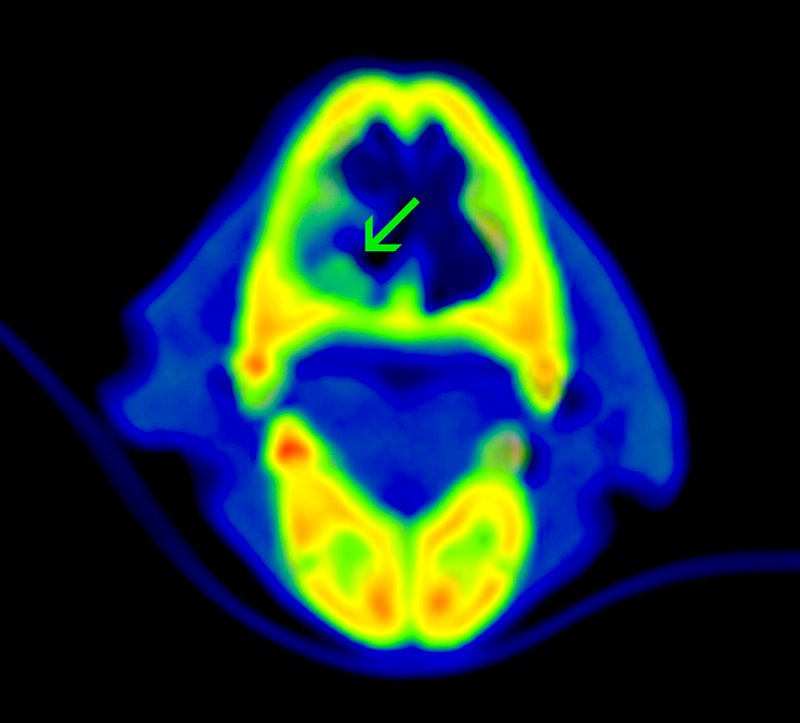

La cirugía termina cando se ha eliminado la masa por completo, además de los márgenes de seguridad que hayamos establecido, si nuestra intención es curativa o cuando consigamos disminuir si tamaño a aquel que elimine los sintomas y mejore la calidad de vida del animal si nuestro planteamiento terapeutico es paliativo. Las imágenes muestran una tomografía posoperatoria del mismo punto anatómico una vez eliminado el tumor.